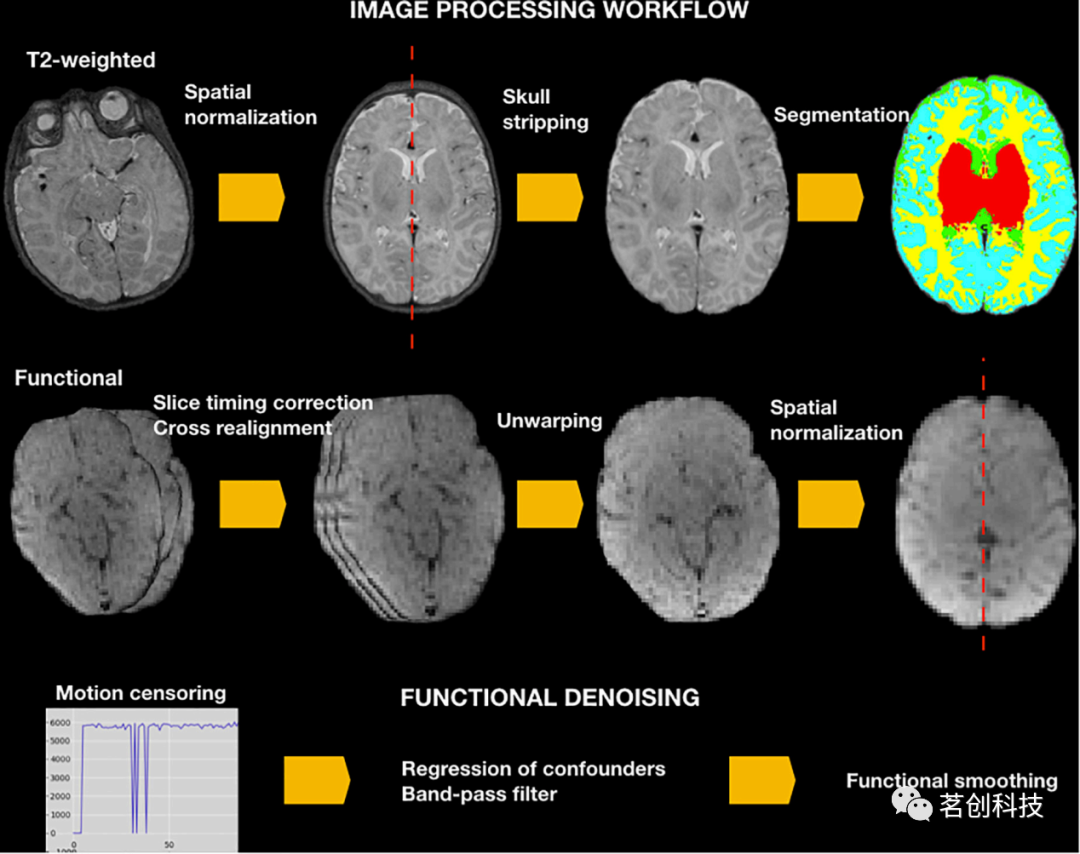

流程概述

NeoRS是在Matlab上开发的新生儿rsfMRI数据处理管道,是在FSL 6.0.3.1,AFNI 20.2.10和SPM 12等知名的开源神经成像工具上开发的命令,可以在MacOS和Linux操作系统上运行。NeoRS旨在适应从不同制造商设备上获取的MRI数据,可适用于并行环境,允许同时对多个被试数据进行处理。更多详情请参见图2中的NeoRS工作流程。

图2.新生儿静息态功能连接处理和去噪的NeoRS工作流程。

为了确保图像与标准模板的方向对齐,在使用FSL的fslreorient2std进行其他数据处理过程之前,对结构和功能数据执行标准重定向。此外,为了保证NeoRS的准确性能,每个处理步骤的输出文件都保存在名为Output_files的文件夹中。各种操作步骤不是强制性的,比如时间层校正或畸变校正,可以通过在主文件中将函数参数设置为0,即可手动关闭。有关输入配置的示例见图3。